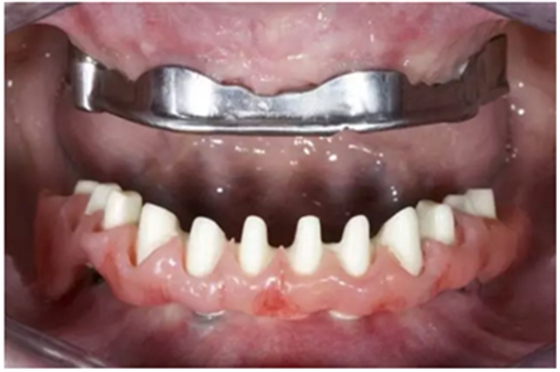

試戴上頜NobelProcera CAD/CAM海德式桿卡(IBO)以及下頜NobelProcera二氧化鋯種植橋(PIB)。